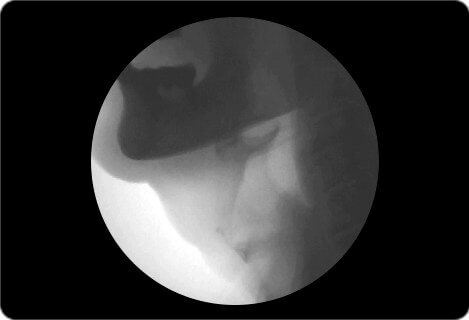

VF検査(嚥下造影検査)

嚥下造影検査は飲み込みの機能を評価する検査です。飲み込みは、外からではとても分かりにくいものです。

透視下にて造影剤を混ぜた物を食べ、飲食物がどのような経路で入っていくかを確認します。飲み込みの問題点を明らかにする、最も有効な検査です。検査後は主治医より結果説明、結果をふまえて今後の方針について話し合います。

X線による画像